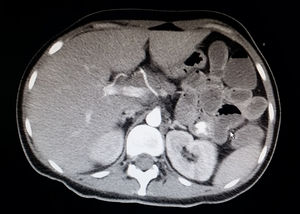

A 24-year-old man had been diagnosed with colic Crohn's disease 8 years earlier and treated with azathioprine and adalimumab due to concomitant perianal disease. He was admitted due to fever for the past week associated with an increased number of bowel movements with occasional traces of blood and an abnormal liver panel (AST 127U/l, ALT 130U/l). A physical examination revealed inguinal and supraclavicular lymphadenopathy measuring a millimetre. Serologies for viral hepatitis and HIV, blood cultures, urine culture, faecal culture, and determination of C. difficile toxin were negative. A CT scan of the chest and abdomen ruled out lymphoproliferative impairment and ileocolonoscopy ruled out CD activity. During admission, his diarrhoea spontaneously remitted, whereas his fever and liver abnormalities persisted for several days with no other associated symptoms. Finally, serology enabled a diagnosis of primary CMV infection (positive for IgM, negative for IgG and a VL of 23,000copies). Treatment with intravenous ganciclovir was started and maintained for 12 days, and immunosuppression was suspended. The patient followed a good clinical course with good laboratory values. Subsequently, treatment was started with valganciclovir until the VL became negative, and the prior immunosuppression was reintroduced.